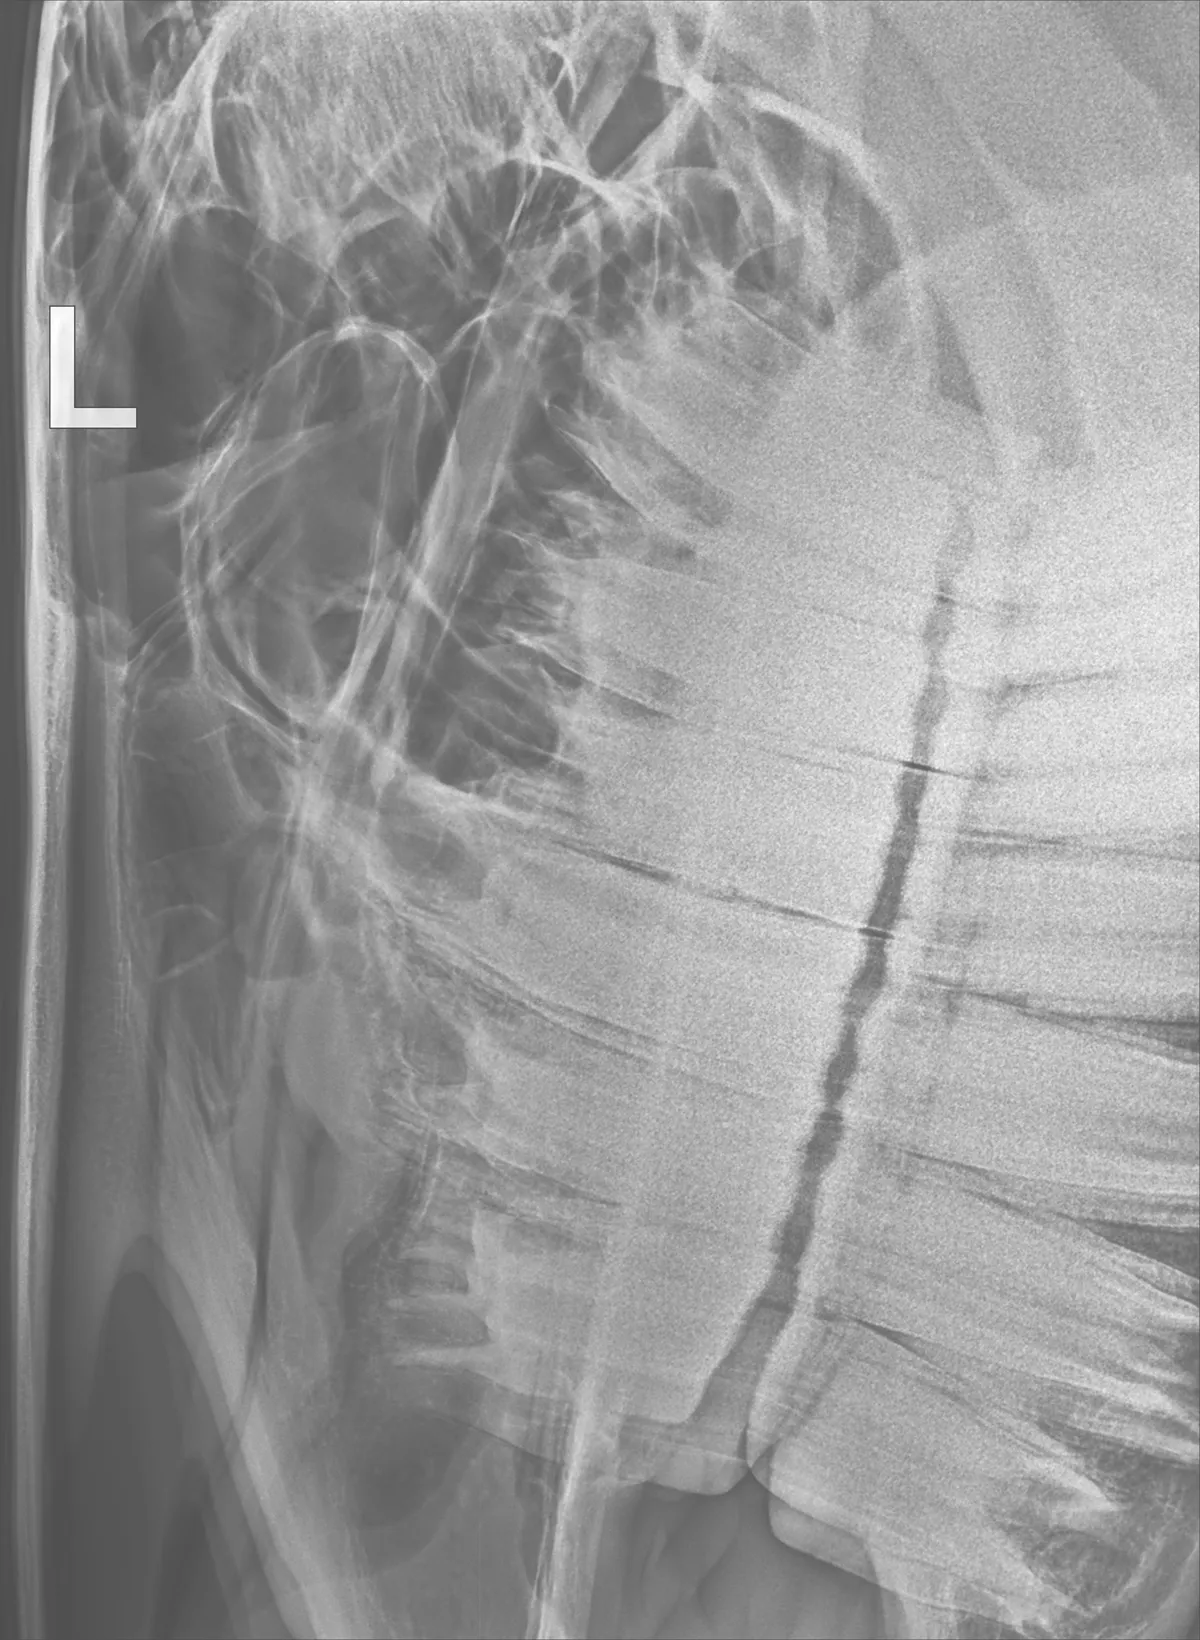

Equine Dentistry

CCEV provides both routine and advanced equine dental care, ensuring your horse’s dental health is maximised for both performance and longevity.

Regular equine dental health checks under sedation are essential for maximising dental longevity, oral health, physical condition, performance, and long-term wellbeing. We combine routine care with advanced techniques to meet the needs of every horse.

Christopher holds an advanced veterinary practice certificate in equine dentistry, which involves several years of additional training. So you can rest assured knowing your horse is in the best hands.